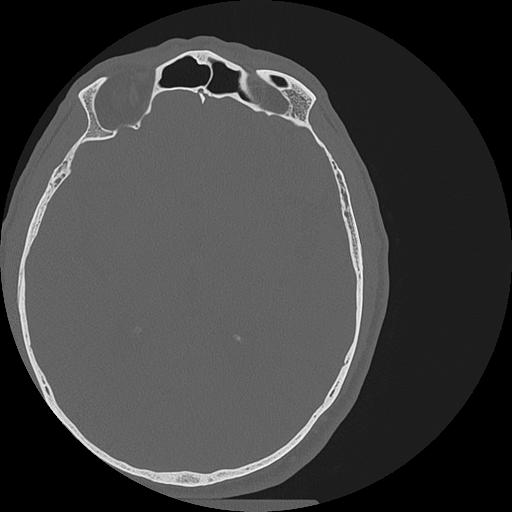

7 HUESO,,Vol,0.5,HUESO,,